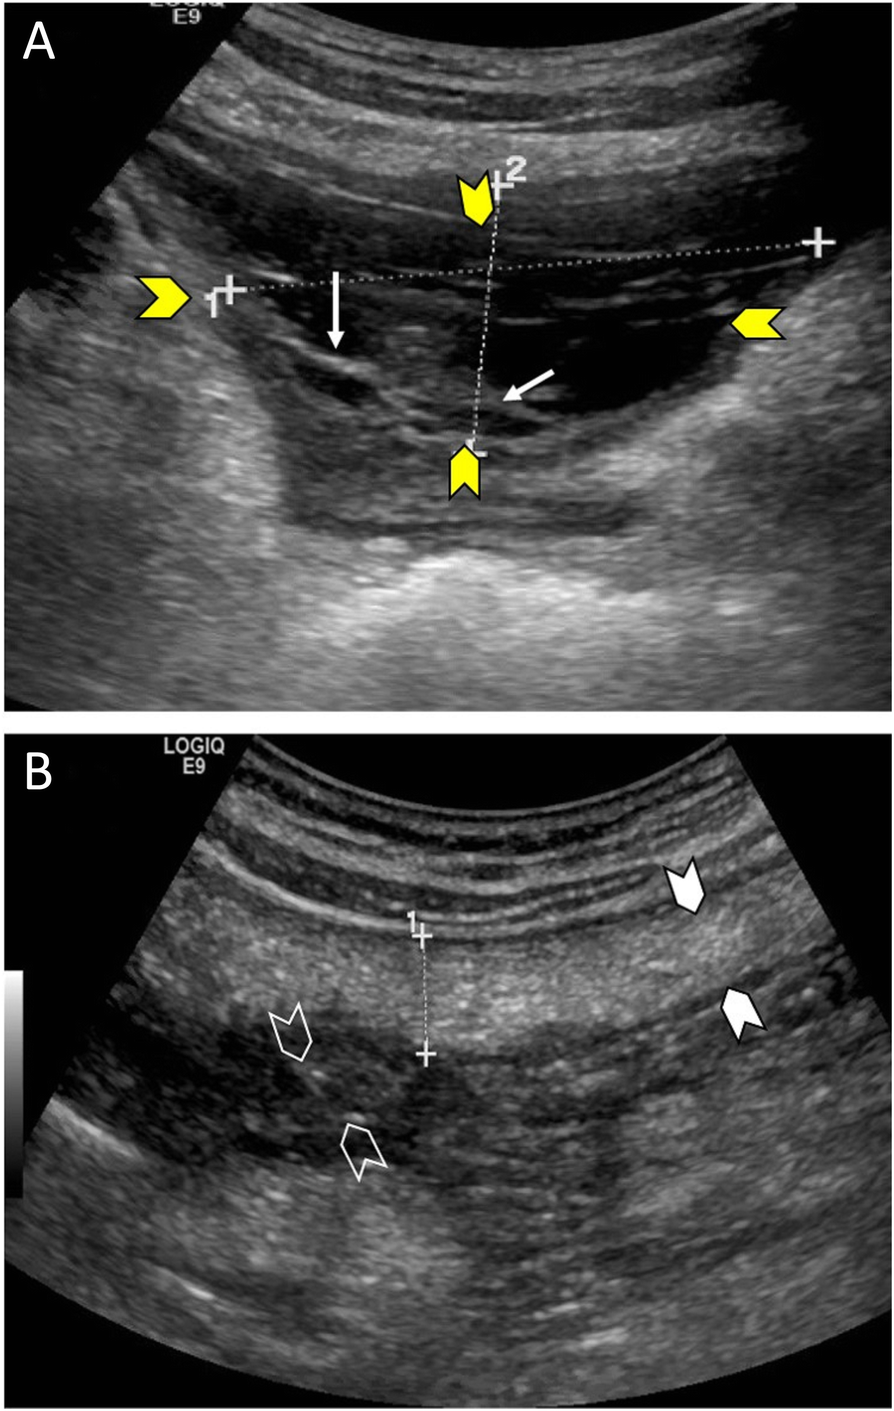

Fig. 1

A 29-year-old man presented with shortness of breath, generalized abdominal pain, and fatigue. Abdominal ultrasound scan showed ascites (A, yellow arrow heads) with loculations (A, white arrows) in the pelvis and the left iliac fossa. The peritoneum (B, white arrow heads) and omentum (B, empty arrow heads) were thickened. Peritoneal and pleural fluid cytology were suggestive of an inflammatory tuberculous process. The patient responded to the anti-tuberculous therapy